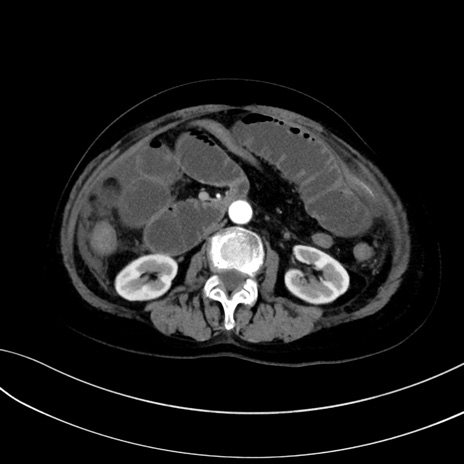

症例13 CT(横断像)1日半後